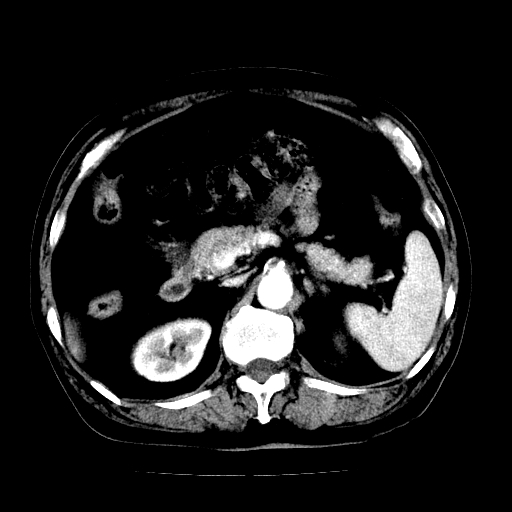

男,71岁,皮肤黄染四天。

肝内外胆管及胆总管上段扩张,考虑为梗阻所致,建议mrcp检查。

考虑胆总管癌并肝内外胆管扩张。

胆管癌并肝内外胆管扩张。

支持考虑胆总管癌并肝内外胆管扩张。 局部应薄扫。心包钙化。

胰腺上端胆总管内见软组织影,强化不明显,结合临床,还是考虑低位梗阻性黄疸,胆总管癌可能性大